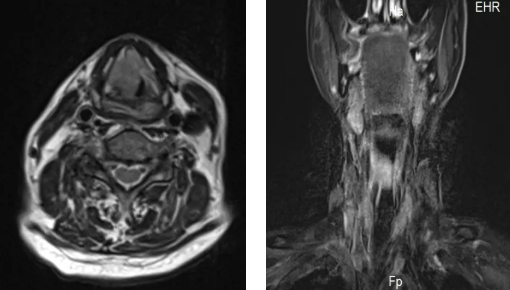

84歲的趙大爺因喉部腫瘤,三個(gè)月前做了氣道改造手術(shù),平時(shí)靠一根氣管套管輔助呼吸。沒(méi)想到一天深夜,這根“生命管”突然脫落,頸部的人工氣道口也很快閉合。老人呼吸困難,被家人緊急送往隨州市中心醫(yī)院。 情況萬(wàn)分 ...